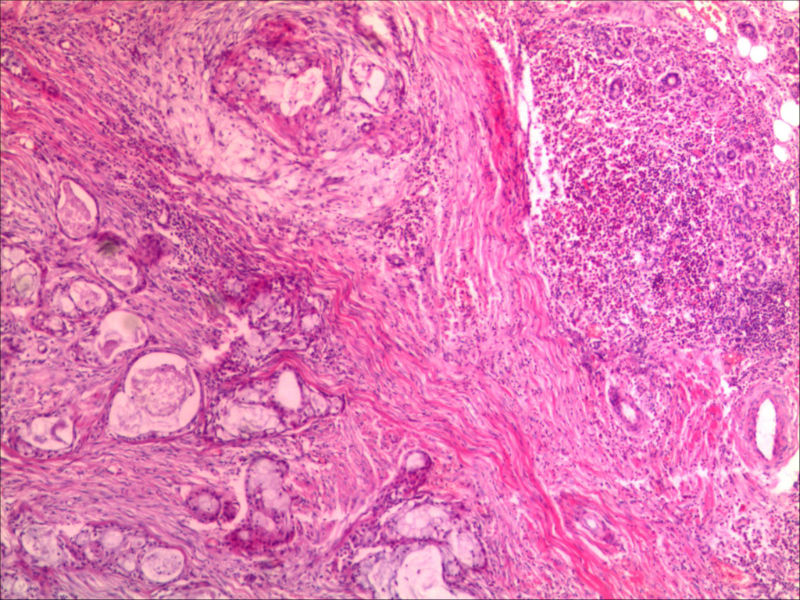

典型的黏液表皮样癌,低度恶性。

本例可以看到典型的产粘液细胞、鳞状细胞、中间细胞和透明细胞,因为产粘液细胞多,甚至形成粘液湖,加之包块似有包膜,分界清楚,应该考虑粘液表皮样癌(低度恶性)。